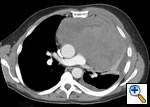

Any anterior mediastinal mass (Figures 1, 2) must be considered suspect for germ cell tumor, especially in a young male. Errors in diagnosis are not uncommon and can result in mismanagement of a potentially curable patient. All patients with an anterior mediastinal mass should have alpha-fetoprotein (AFP), β-human chorionic gonadotropin (β-HCG), and lactate dehydrogenase (LDH) levels drawn at the outset. The different types of germ cell histologies are shown in Figure 3.

Figure 2: Computed tomography of mediastinal germ cell tumor